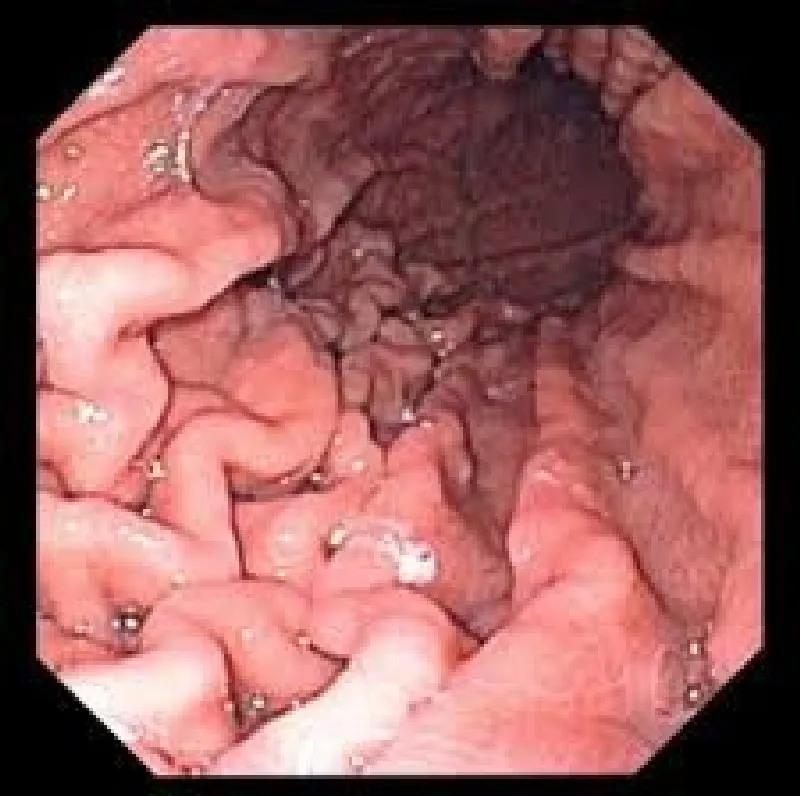

São diversos os tipos de exames por imagem, que precisam de uma boa qualidade de impressão, como a impressora endoscopia – um exame para análise da mucosa do esôfago, do estômago e da primeira parte do intestino delgado.

As imagens são captadas por meio de um cateter, introduzido pela boca do paciente. No entanto, para obter uma imagem de qualidade real, é preciso investir em equipamentos e impressoras de alta definição.